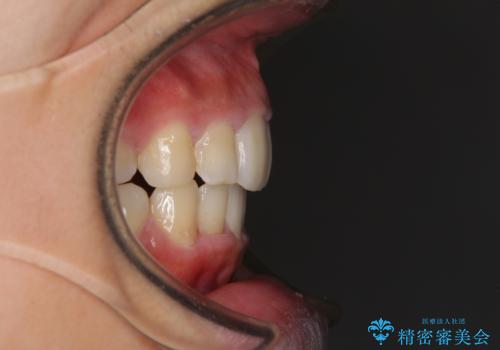

口元を積極的に引っ込めるために、上下左右の第一小臼歯を4本抜歯することとしました。

しっかりと通院するようになってからは順調に治療が進み、横顔の印象が変わるほどスッキリとした口元となりました。